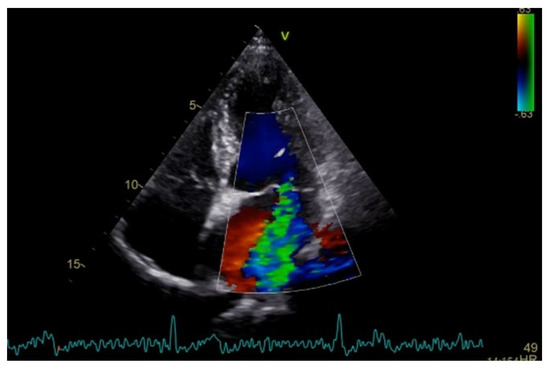

Severe mitral regurgitation was identified, manifested by an eccentric regurgitant jet and associated left atrial dilatation (Figure 4). Moderate tricuspid regurgitation with right atrial dilatation was also present. Both the left and right ventricles were of normal size and function. Global longitudinal strain was preserved for both ventricles, with an average of −22.9% for the left ventricle and −22.0% for the right ventricle, although a mild degree of dispersion in longitudinal strain peaks was observed (Figure 5).

Figure 4.

Apical four chamber view showing severe mitral regurgitation with left atrial dilatation.

Figure 5.

2D speckle-tracking echocardiography used as a tool for assessing left ventricular systolic performance (GLS average −22.9%), with some degree of dispersion in longitudinal strain peaks.